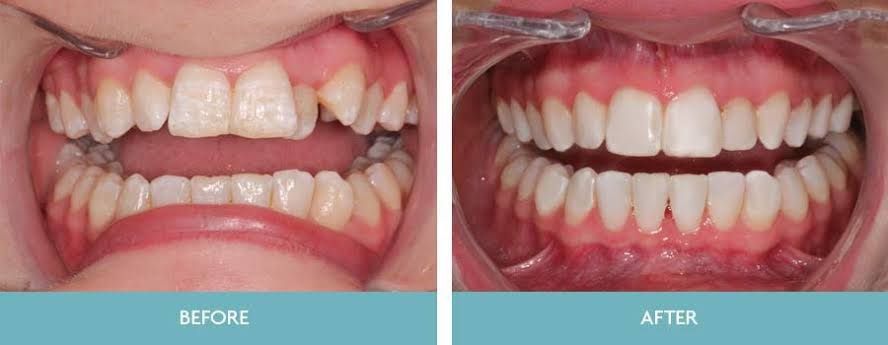

MOST POPULAR TREATMENTS

What we offer